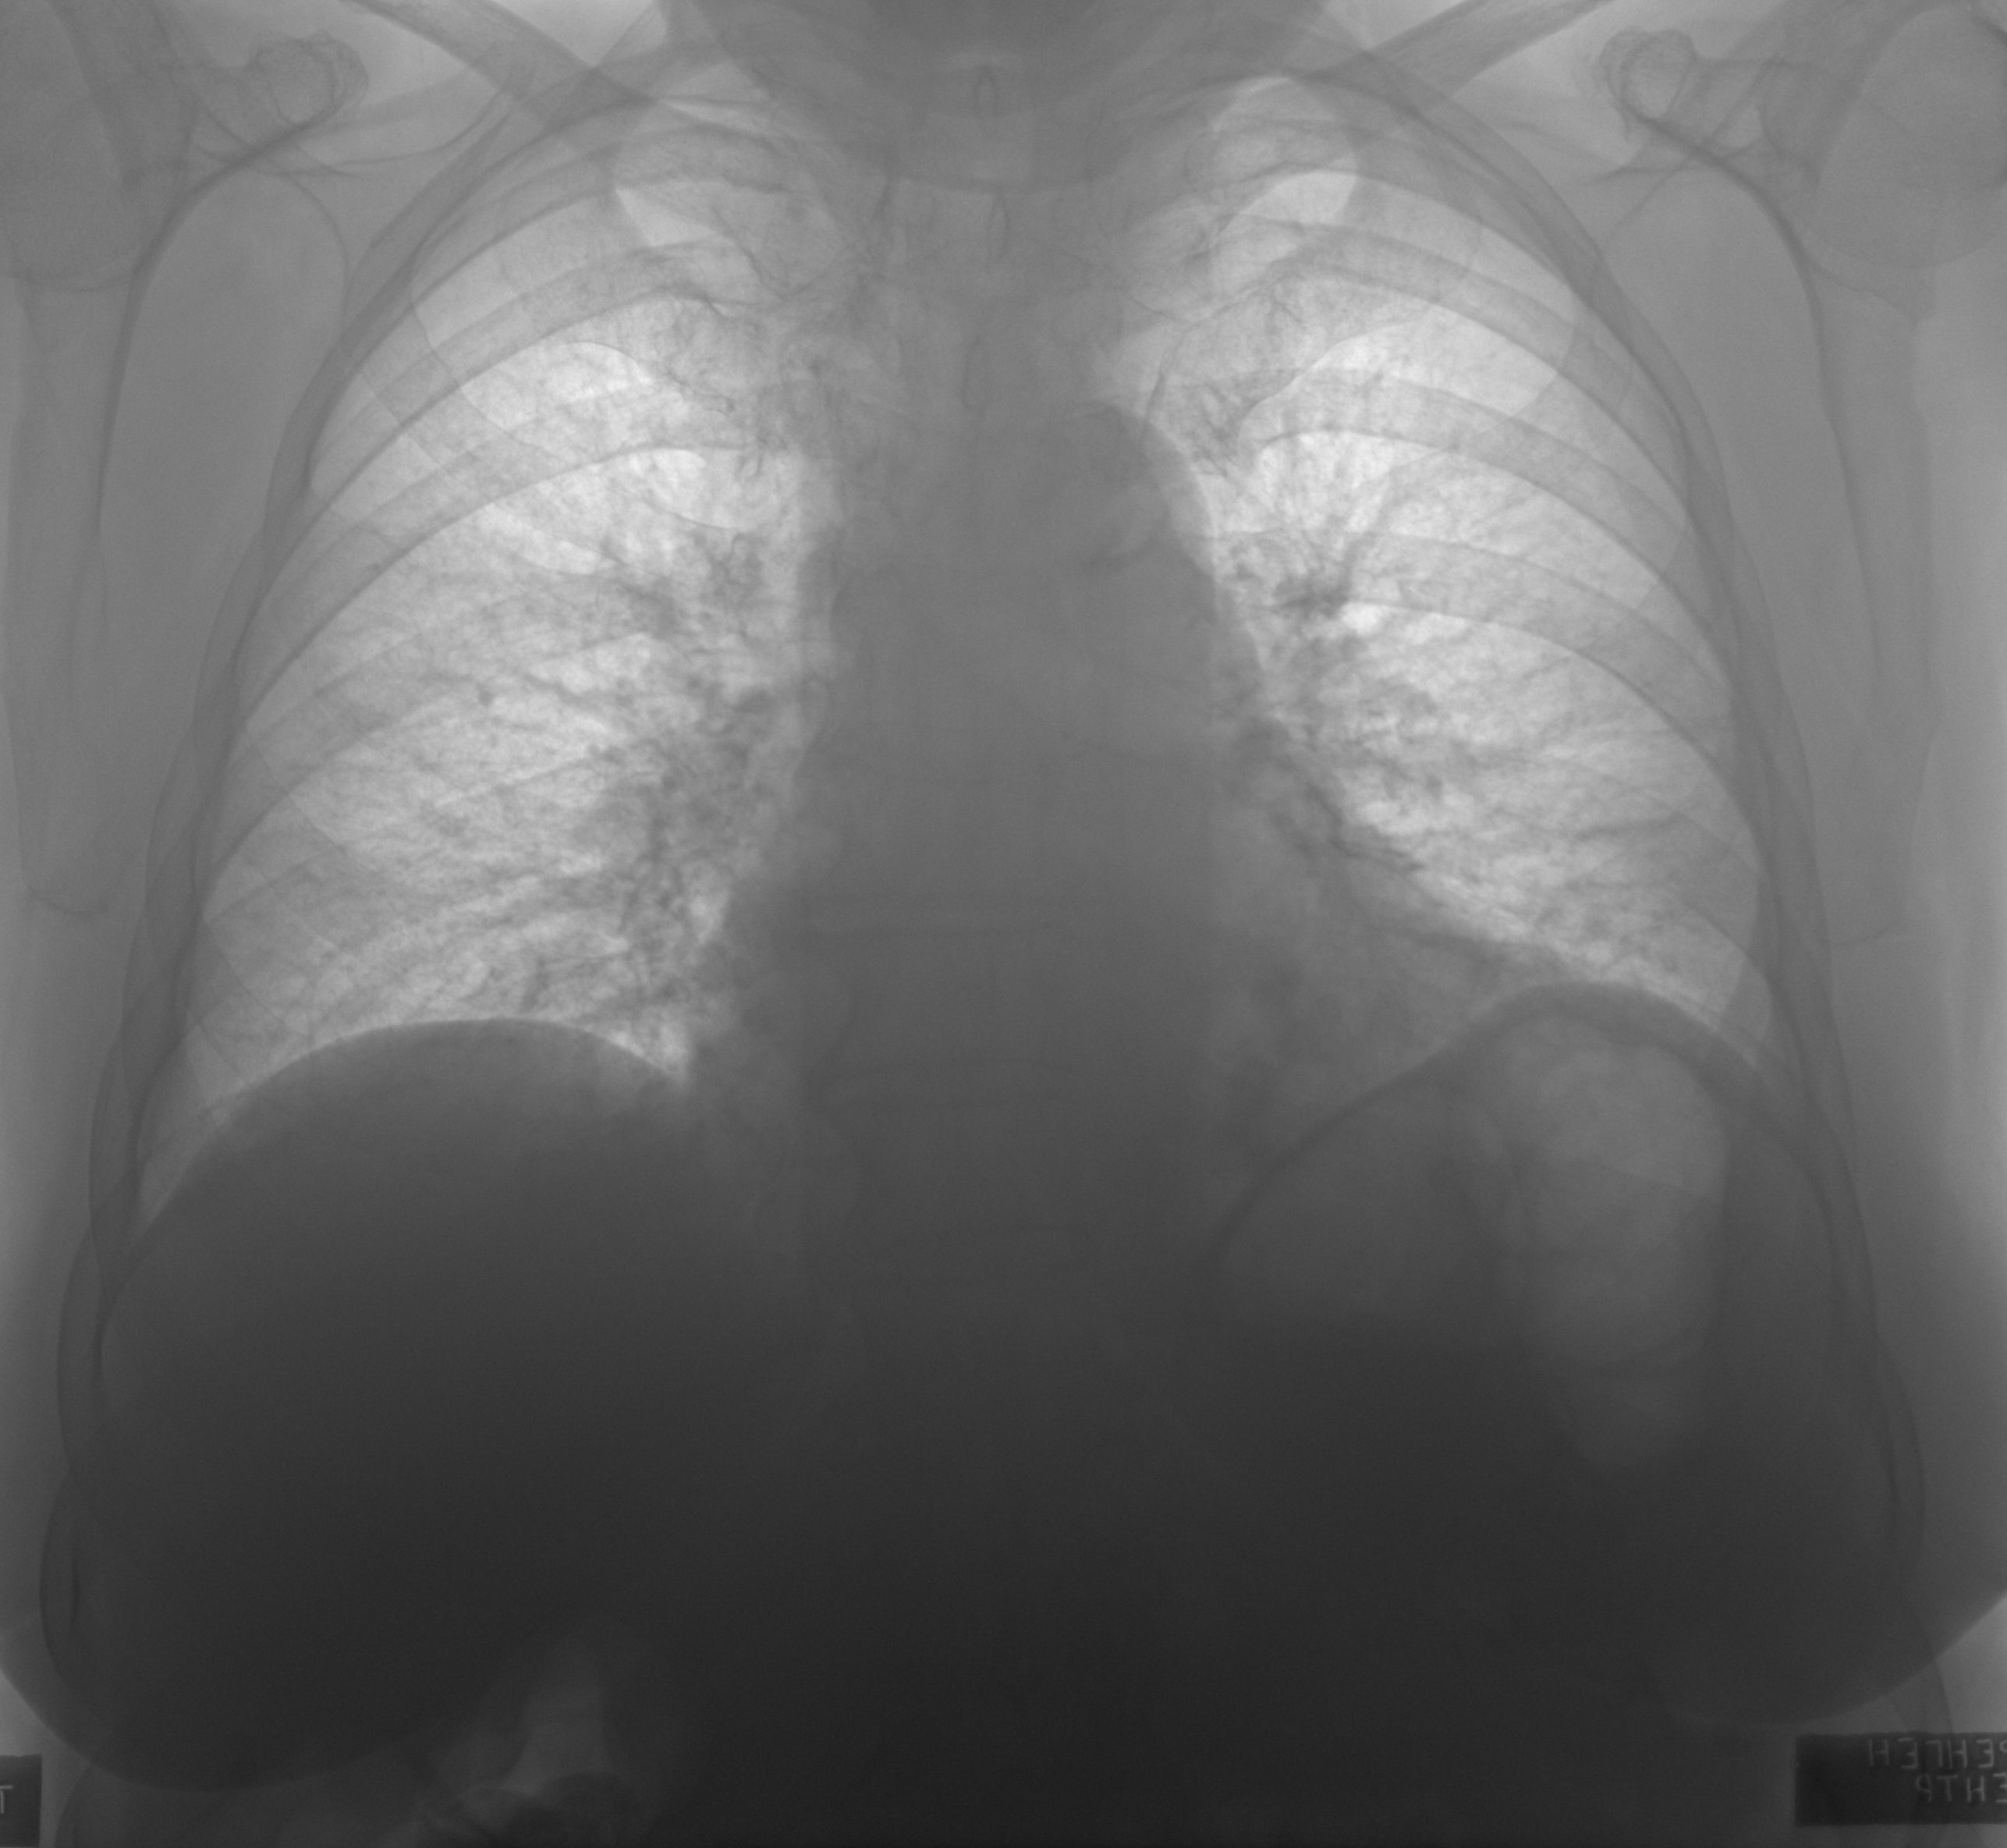

15052020 Плевосклероз